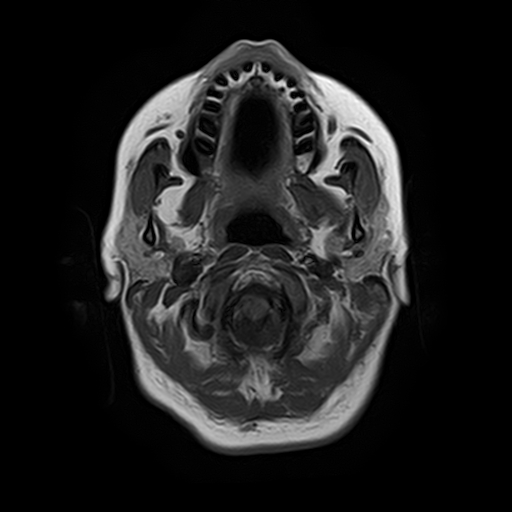

Височно-нижнечелюстной сустав является парным комбинированным суставом и имеет сложное строение. В него входят суставные ямки височной кости, суставные головки нижней челюсти и расположенные между ними хрящевые пластинки – мениски, выполняющие роль амортизаторов.

Сустав имеет мощный связочный аппарат, который позволяет ему выдерживать большую нагрузку при пережевывании пищи. Сложное строение и значительные нагрузки способствуют развитию в суставе дегенеративно-дистрофических и воспалительных заболеваний.

Магнитно-резонансная томография является наиболее точным и эффективным методом диагностики поражения височно-нижнечелюстных суставов, так как позволяет получить детальную информацию о состоянии не только костей, но и связочного аппарата, хрящей, менисков, жевательных мышц, окружающих мягких тканей.

При проведении магнитно-резонансной томографии на изображениях визуализируются: височная кость, головка мыщелкового отростка нижней челюсти, суставная щель. Помимо костных структур МРТ позволяет оценить состояние мягких тканей – внутрисуставного диска и связочного аппарата височно-нижнечелюстного сустава, жевательных мышц.